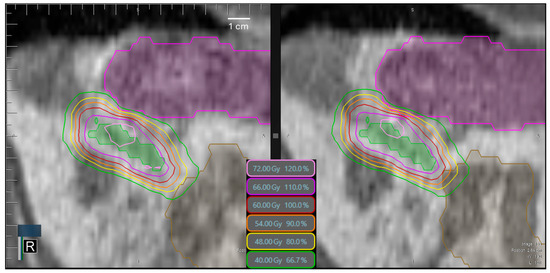

3.3. Target Volume Coverage

3.6. Time-Dependence of PTV Coverage and OAR Overdosage